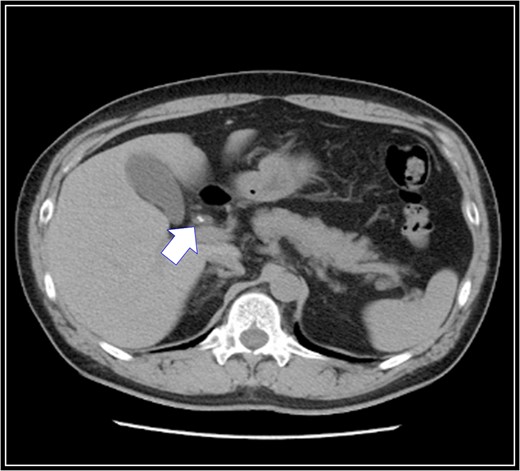

A 48-year-old Japanese man experienced abdominal pain after dinner. He underwent computed tomography (CT), and we observed stones in his cystic duct (Fig. 1). Hematological findings showed no liver dysfunction. A magnetic resonance cholangiopancreatography (MRCP) scan demonstrated that the right accessory hepatic duct branching from the cystic duct dominated an anterior segment of the right hepatic lobe (Fig. 2). Therefore, we diagnosed him as cholelithiasis with an anomalous biliary tract, and LC was planned.

Preoperative magnetic resonance cholangiopancreatography scan. The right accessory hepatic duct branching from the cystic duct (black arrow) dominates an anterior segment of the right hepatic lobe.